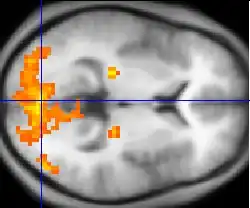

PET, fMRI, fNIRS and fUS can measure localized changes in cerebral blood flow related to neural activity. These changes are referred to as activations. Regions of the brain which are activated when a subject performs a particular task may play a role in the neural computations which contribute to the behaviour. For instance, widespread activation of the occipital lobe is typically seen in tasks which involve visual stimulation (compared with tasks that do not). This part of the brain receives signals from the retina and is believed to play a role in visual perception.

Traditional "activation studies" focus on determining distributed patterns of brain activity associated with specific tasks. However, scientists are able to more thoroughly understand brain function by studying the interaction of distinct brain regions, as a great deal of neural processing is performed by an integrated network of several regions of the brain. An active area of neuroimaging research involves examining the functional connectivity of spatially remote brain regions. Functional connectivity analyses allow the characterization of interregional neural interactions during particular cognitive or motor tasks or merely from spontaneous activity during rest. FMRI and PET enable creation of functional connectivity maps of distinct spatial distributions of temporally correlated brain regions called functional networks. Several studies using neuroimaging techniques have also established that posterior visual areas in blind individuals may be active during the performance of nonvisual tasks such as Braille reading, memory retrieval, and auditory localization as well as other auditory functions.[3]